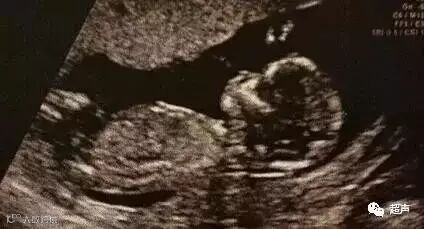

1)6-7周的早孕检查(ultrasound dating):主要确认孕周,看究竟是宫内妊娠还是宫外孕,单胎还是双胎(确认绒毛膜性)或多胎,胚胎是死的还是活的。